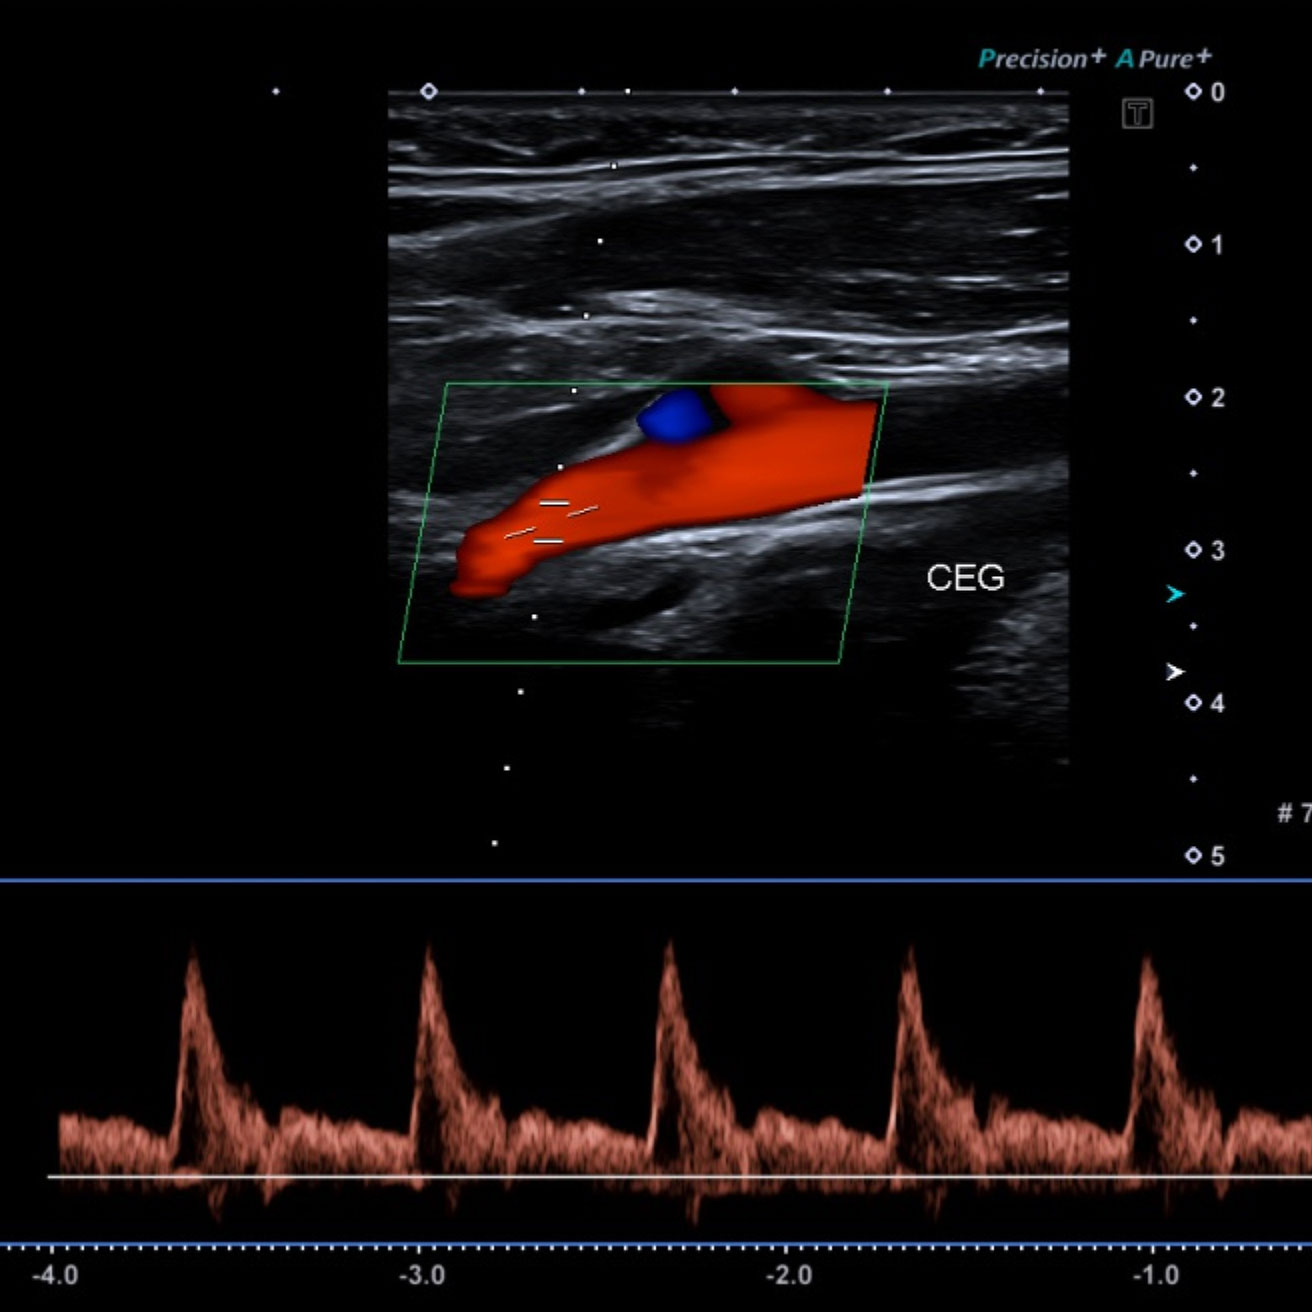

Le Doppler, qu’il soit veineux ou artériel, est un examen d’imagerie utilisant les ultrasons (échographie).

Il permet d’étudier les veines et les artères.

Le Doppler utilise les ultrasons, comme une échographie classique.

• Vous entendrez parfois un bruit pulsé, correspondant au flux sanguin enregistré en temps réel : c'est normal.